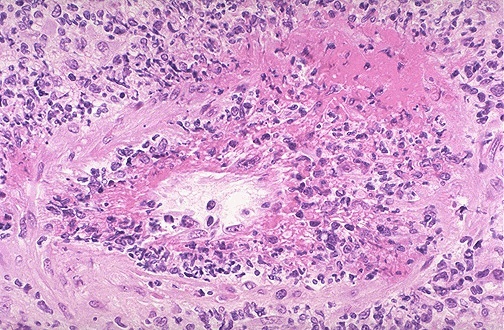

| At high power, the vasculitis is seen to involve a renal artery branch. This is a necrotizing granulomatous vasculitis. In this case, the anti-neutrophil cytoplasmic autoantibody (ANCA) serology was positive and a diagnosis of Wegener granulomatosis was made. This patient also had pulmonary involvement with this disease. |